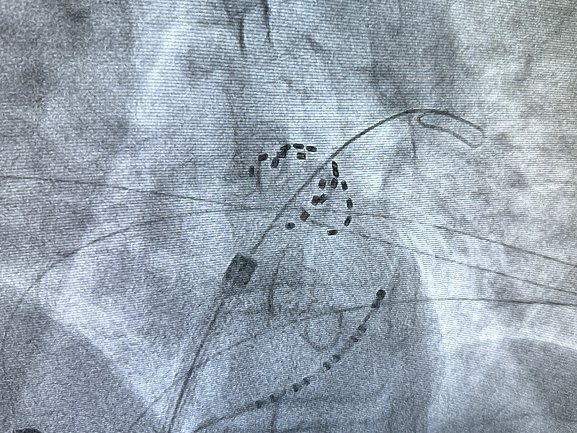

确认导管可以打出网篮、花瓣两种形态

FARADRIVE网篮、花瓣两种形态消融肺静脉